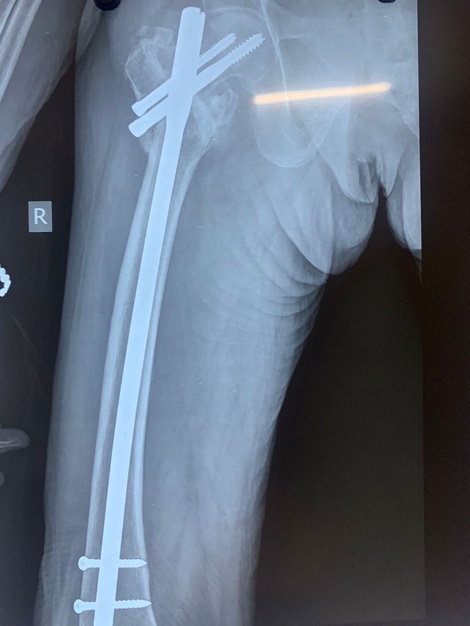

Fig. 1: Left IT femur #

Initially, closed reduction was attempted using internal rotation and longitudinal traction. In cases where closed reduction was not feasible, a mini-open approach was employed. This involved making a small longitudinal incision approximately 5 cm proximal to greater trochanter. Gluteal fascia was incised, and gluteus medius was split longitudinally to access tip of trochanter. The correct entry point for nail was determined using fluoroscopy, and a guide wire was advanced from trochanter to medulla (fig. 2).